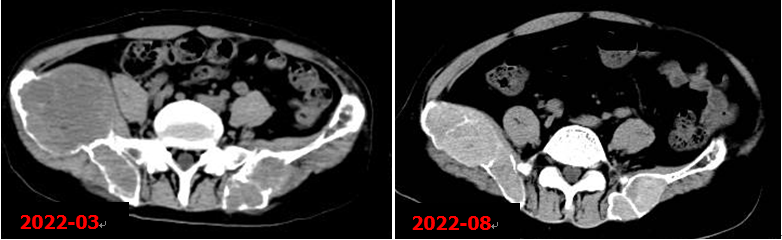

右側甲狀旁腺腺瘤切除術后,甲狀旁腺MIBI顯像未見明確病灶組織殘留征象。術后5個月本院復查CT示右髂骨病變明顯縮小。